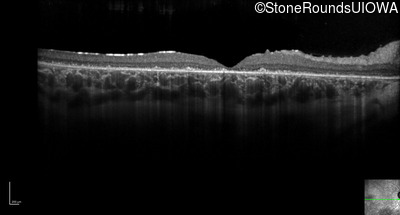

Optical Coherence Tomography - Left - 20/100 -2 sc

Exemplar / OCT Stack

OCT Stack